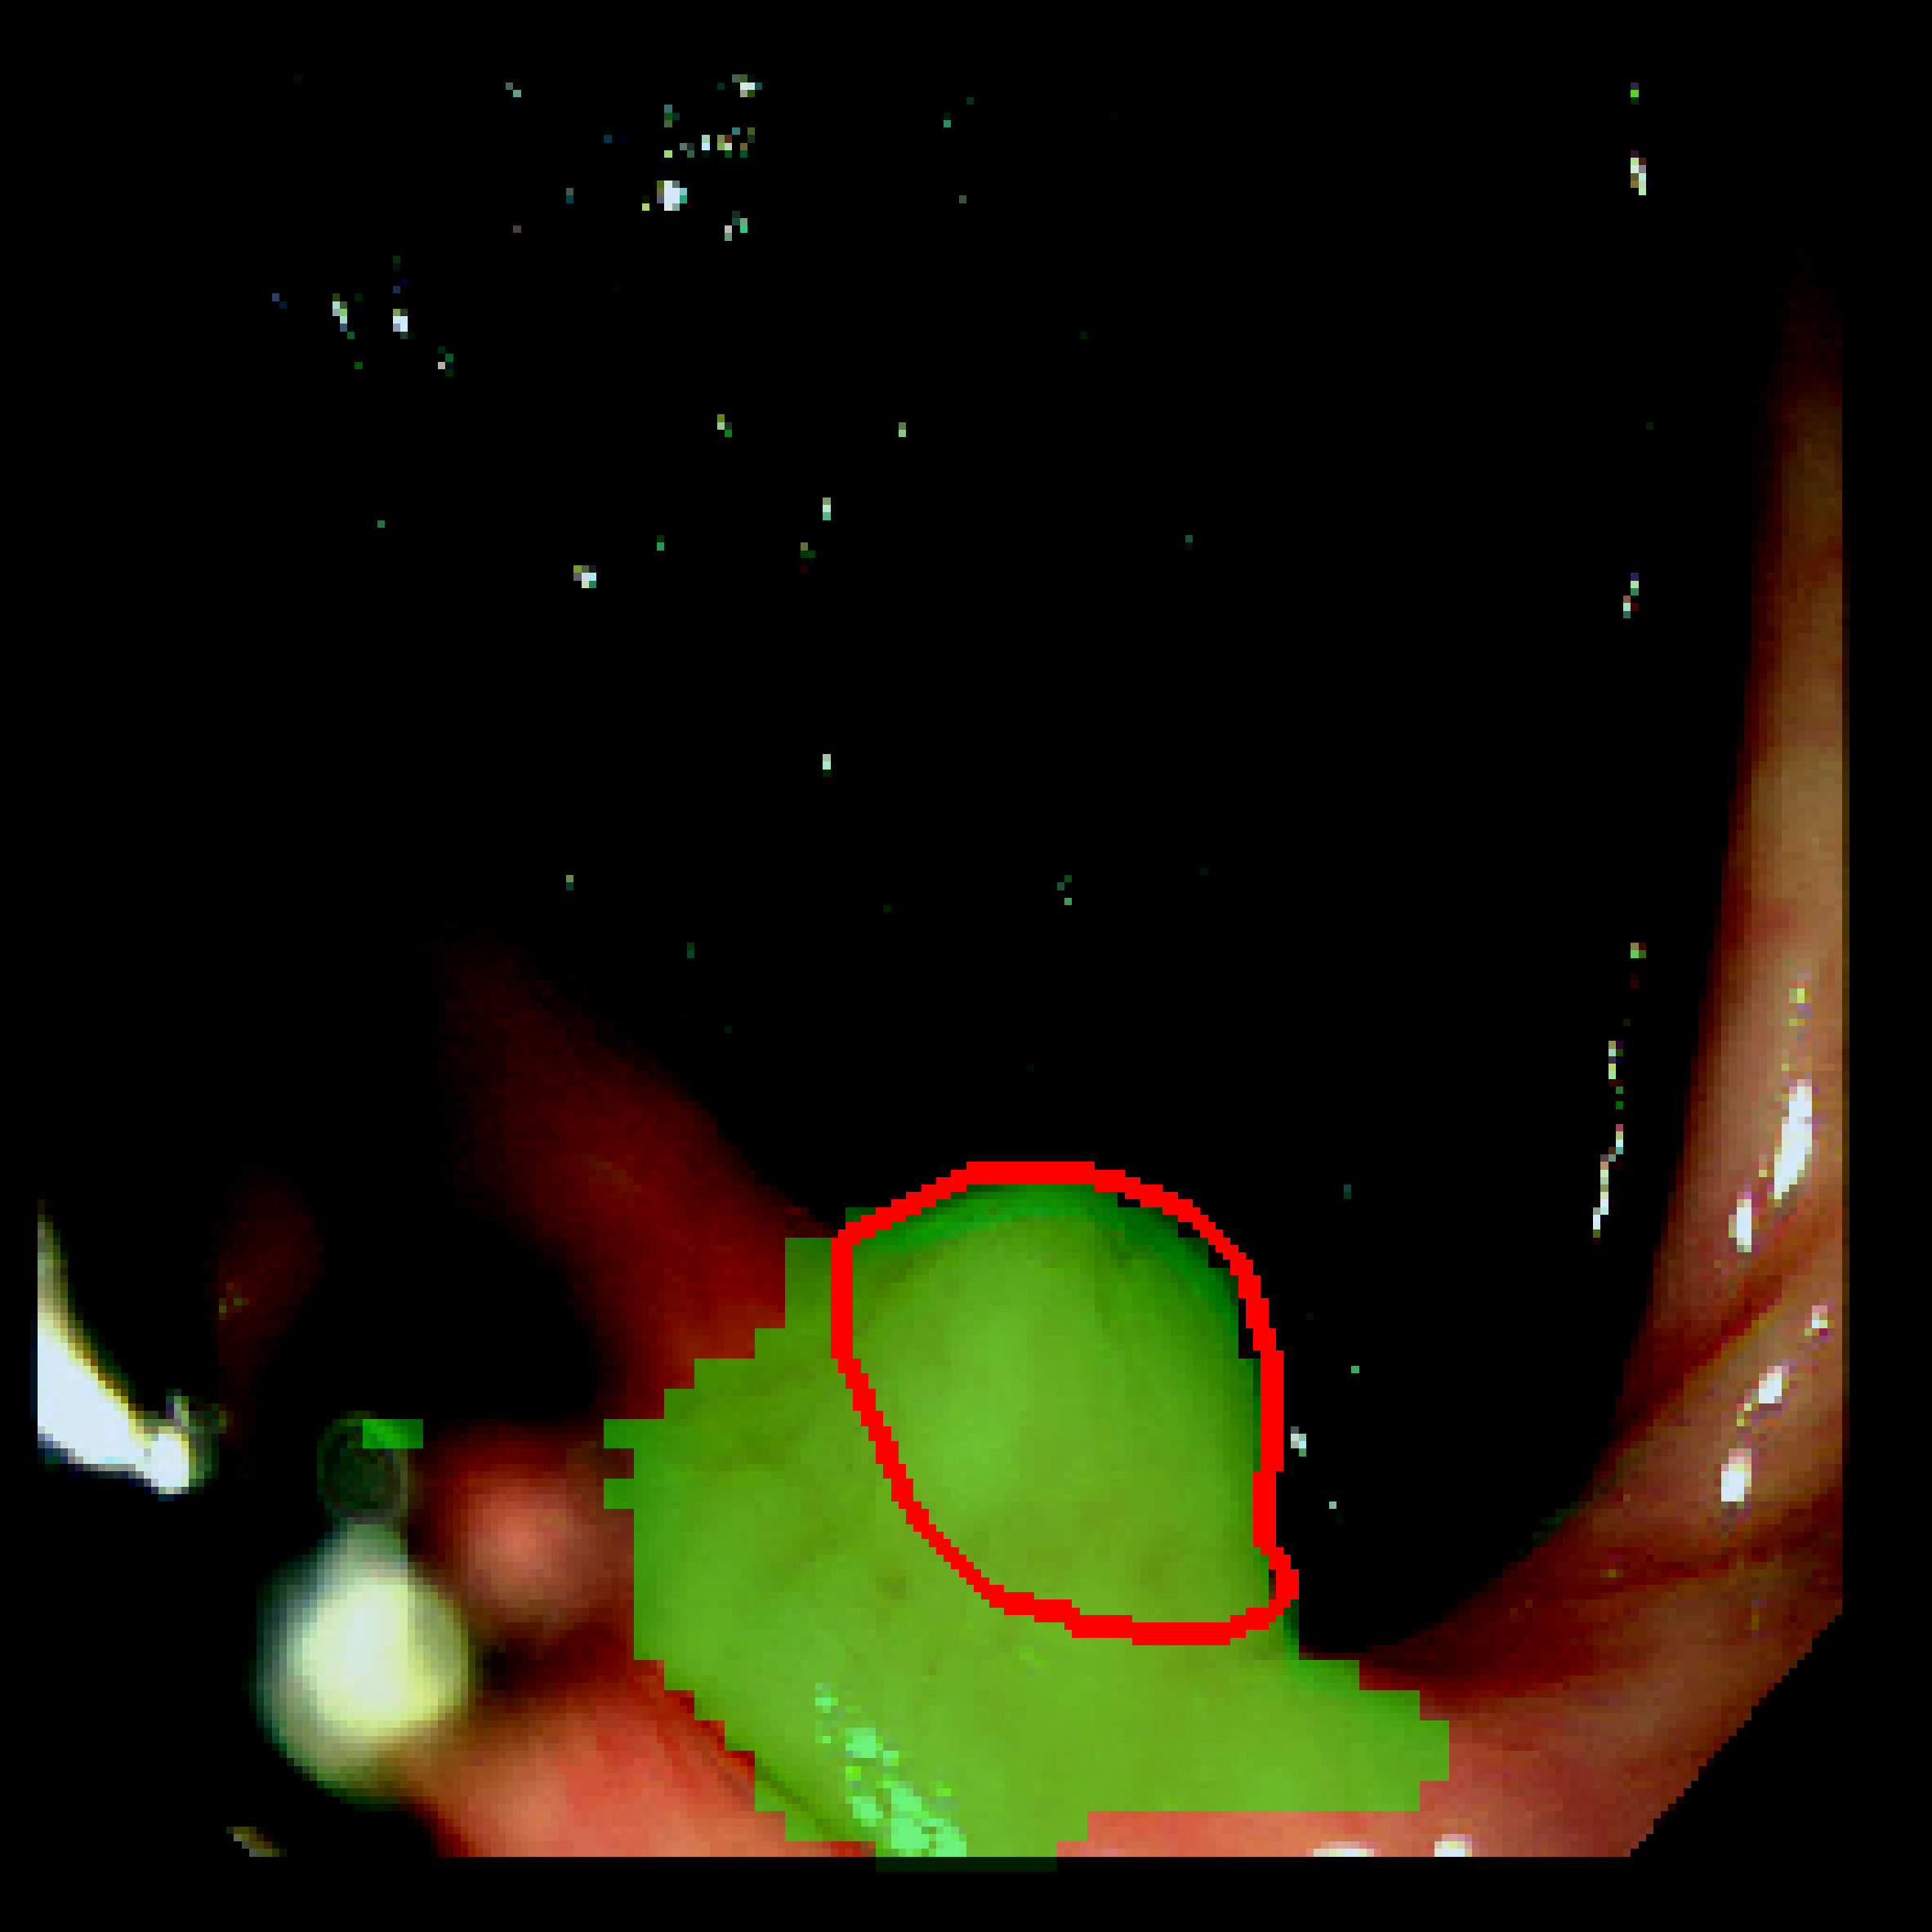

3.3 Qualitative results

Table 3: Qualitative results of different methods, \Circle and \CIRCLE denote groundtruth and predicted mask, respectively.

SAM MedSAM SAM-Med2D CPC-SAM KnowSAM Ours

5% Promise [Uncaptioned image] [Uncaptioned image] [Uncaptioned image] [Uncaptioned image] [Uncaptioned image] [Uncaptioned image]

10% Promise [Uncaptioned image] [Uncaptioned image] [Uncaptioned image] [Uncaptioned image] [Uncaptioned image] [Uncaptioned image]

5% Colon [Uncaptioned image] [Uncaptioned image] [Uncaptioned image] [Uncaptioned image] [Uncaptioned image] [Uncaptioned image]

10% Colon [Uncaptioned image] [Uncaptioned image] [Uncaptioned image] [Uncaptioned image] [Uncaptioned image] [Uncaptioned image]

For the qualitative results shown in Tab. 3, our method consistently produces more accurate and compact segmentation results for most cases in the PROMISE12 and COLON datasets, effectively capturing the prostate and polyp boundaries while suppressing background noise. In contrast, other approaches tend to over-segment the target regions, leading to the inclusion of irrelevant surrounding tissues. These results visually demonstrate the robustness of our method in handling diverse anatomical variations.